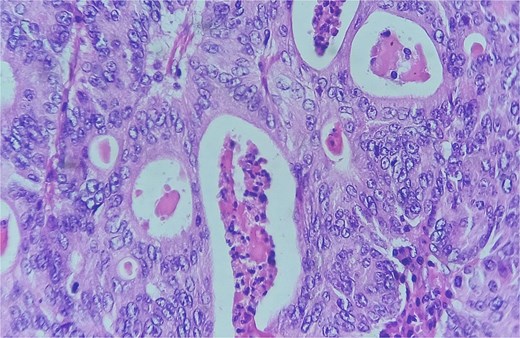

Detail of an area of enteric-type adenocarcinoma composed of neoplastic proliferation of columnar epithelial cells with nuclear atypia, eosinophilic cytoplasm, and a complex tubular and cribriform arrangement with endoluminal necrosis; H&E ×400.